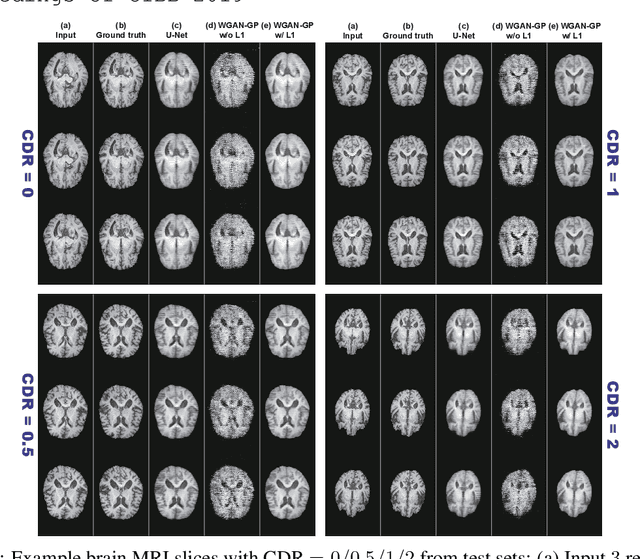

Abstract:Unsupervised learning can discover various unseen diseases, relying on large-scale unannotated medical images of healthy subjects. Towards this, unsupervised methods reconstruct a 2D/3D single medical image to detect outliers either in the learned feature space or from high reconstruction loss. However, without considering continuity between multiple adjacent slices, they cannot directly discriminate diseases composed of the accumulation of subtle anatomical anomalies, such as Alzheimer's Disease (AD). Moreover, no study has shown how unsupervised anomaly detection is associated with either disease stages, various (i.e., more than two types of) diseases, or multi-sequence Magnetic Resonance Imaging (MRI) scans. Therefore, we propose unsupervised Medical Anomaly Detection Generative Adversarial Network (MADGAN), a novel two-step method using GAN-based multiple adjacent brain MRI slice reconstruction to detect various diseases at different stages on multi-sequence structural MRI: (Reconstruction) Wasserstein loss with Gradient Penalty + 100 L1 loss-trained on 3 healthy brain axial MRI slices to reconstruct the next 3 ones-reconstructs unseen healthy/abnormal scans; (Diagnosis) Average L2 loss per scan discriminates them, comparing the ground truth/reconstructed slices. For training, we use 1,133 healthy T1-weighted (T1) and 135 healthy contrast-enhanced T1 (T1c) brain MRI scans. Our Self-Attention MADGAN can detect AD on T1 scans at a very early stage, Mild Cognitive Impairment (MCI), with Area Under the Curve (AUC) 0.727, and AD at a late stage with AUC 0.894, while detecting brain metastases on T1c scans with AUC 0.921.

Abstract:Unsupervised learning can discover various unseen diseases, relying on large-scale unannotated medical images of healthy subjects. Towards this, unsupervised methods reconstruct a single medical image to detect outliers either in the learned feature space or from high reconstruction loss. However, without considering continuity between multiple adjacent images, they cannot directly discriminate diseases composed of the accumulation of subtle anatomical anomalies, such as Alzheimer's Disease (AD). Moreover, no study shows how unsupervised anomaly detection is associated with disease stages. Therefore, we propose a two-step method using Generative Adversarial Network-based multiple adjacent brain MRI slice reconstruction to detect AD at various stages: (Reconstruction) Wasserstein loss with Gradient Penalty + L1 loss---trained on 3 healthy slices to reconstruct the next 3 ones---reconstructs unseen healthy/AD cases; (Diagnosis) Average/Maximum loss (e.g., L2 loss) per scan discriminates them, comparing the reconstructed/ground truth images. The results show that we can reliably detect AD at a very early stage with Area Under the Curve (AUC) 0.780 while also detecting AD at a late stage much more accurately with AUC 0.917; since our method is unsupervised, it should also discover and alert any anomalies including rare disease.